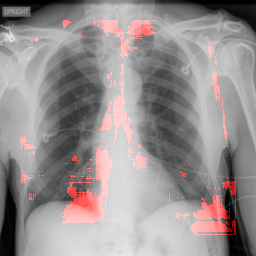

8 Additional Examples of Localization

In this section we show more examples of localization. Few localization samples are shown in Fig. 11. It can be observed that, in the CXRs with Cardiomegaly (Fig. 11(a) and (b)) a fine localization around the heart is observed. In the normal CXRs (Fig. 11(c) and (d)) such localization is not observed. Rather the lowest probabilities are spread out in the CXR image. It is interesting to note that, the localization algorithm gets low probability where the heart is enlarged during cardiomegaly, but the proportion is small compared to the localization in other areas of normal CXRs. In order to observe the performance of the heat map we computed histograms of heat maps of each of the 100 CXRs in the test set for Cardiomegaly detection and average histograms are shown in Fig. 11(e) and (f) for CXRs with Cardiomegaly and normal CXRs, respectively. It is to be noted that, the histograms include both success and failure cases. It can be observed that, for CXRs with Cardiomegaly the classifier is highly sensitive toward Cardiomegaly detection even under occlusion. This indicates that, the classifier primarily looks for local features in a CXR instead of some feature that is spread out in the entire CXR. However, the classifier is not sensitive toward normal CXRs under occlusion. Rather, the probabilities are spread out in the probability spectrum. After that, we analyzed the failure cases where the classifier is unable to classify the image correctly. Two such examples of failure cases are shown in Fig. 12. The localized CXR shown in Fig. 12(a) contains Cardiomegaly whereas the classifier detects it as normal. However, the localization shows that it localizes around heart quite well despite the in accurate classification. On the other hand, Fig. 12(b) shows an example of normal image which has been classified as Cardiomegaly by the classifier. There is stronger localization around the hear that that is observed for normal images as in Fig. 11(c) and (d), however, like those images the localization is spread out.